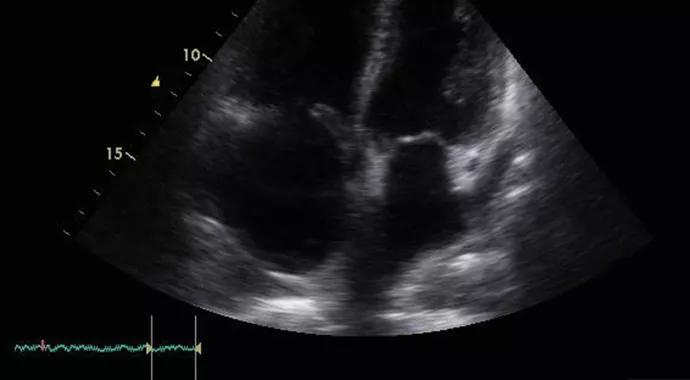

Our retrospective review included approximately 450 patients with a confirmed IM diagnosis seen at Cleveland Clinic between January 2003 and December 2010. PH was “suspected” in this cohort based on transthoracic echocardiography (TTE) (Figure 1) and was “confirmed” by right heart catheterization (RHC) criteria in a subset of these patients. Because the diagnosis of PH should never be established without an RHC, our primary interest was in the subset of patients whose diagnosis was confirmed by RHC.

Figure 1. Transthoracic echocardiogram (apical four-chamber view) in a 66-year-old man with polymyositis associated with antisynthetase (anti-Jo-1) syndrome. The right ventricle (RV) is severely dilated, and the right atrial cavity (RA) is also dilated. The left ventricle (LV) and left atrium (LA) are normal in size and systolic function